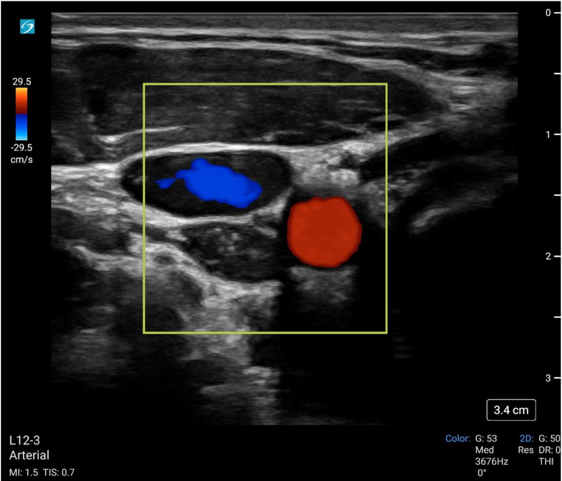

Color

Color doppler ultrasound displays the direction and velocity of flow detected in a defined area. By convention, flow towards the ultrasound is visualized as red and away as blue. To perform color doppler assessment, the operator obtains the standard 2D mode view of the artery and a color doppler box is placed over the vessel.

Literature using color flow doppler to determine ROSC is limited. Humphries et al. describes a case report on the use of color doppler in the prehospital setting to both monitor intra-arrest compression quality as well as to determine ROSC.10

May2025Sonographic Fig 2 color pulse check.pngImage 2: Color flow doppler of the common carotid artery (red) and IJ vein (blue).

Video 2: Color flow doppler of the common carotid artery (with aliasing) during compression of the adjacent IJ vein.